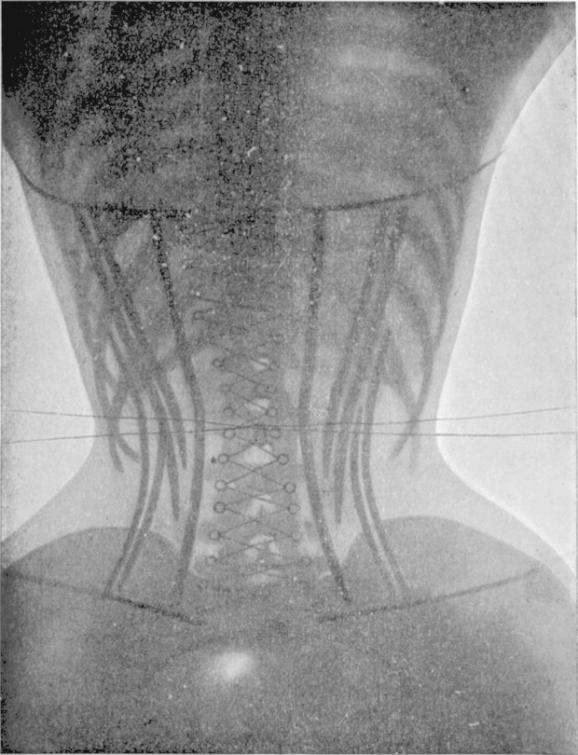

Hình ảnh chụp X-quang của người không mặc áo corset (trên) và người mặc chiếc áo thu nhỏ eo này (dưới).

Khi áo corset trở thành một xu hướng trong những năm 1890, mọi thứ càng trở nên nguy hiểm khi chúng ảnh hưởng đến cả hông và cột sống của phụ nữ bởi họ mặc nó khá thường xuyên. Những người phụ nữ thuộc tầng lớp thượng lưu thường có cơ thể biến dạng đặc biệt với phần ngực, vai và cổ phình to, eo bị thu hẹp lại.